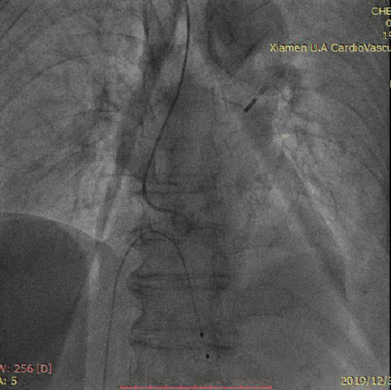

王焱院长结合病人病情及检查结果,考虑晕厥及胸痛的原因为重度主动脉瓣狭窄所导致。病人病情危重,随时可能出现恶性心律失常甚至猝死等危及生命危险。立即行主动脉内球囊反搏术(IABP),IABP是一种对左心功能衰竭的辅助治疗方法。通过物理作用,提高主动脉内舒张压,增加冠状动脉供血和改善心肌功能。现广泛应用于心功能不全等危重病患者的抢救和治疗以及高危心脏病人的术前准备。

IABP

12月24日陈奶奶突发呼吸急促,意识不清,呕吐大量非咖啡色胃内容物,于12月25日凌晨2时再次来我院。入院诊断考虑:心脏病瓣膜病:重度主动脉瓣狭窄、冠心病、三支血管病变、非ST段抬高型心肌梗死、肺部感染(吸入性肺炎可能性大),入院后予维持生命体征、抗血小板、抗感染等支持治疗。12月25日上午8时陈奶奶出现神志淡漠,气喘不适,血氧饱和度及血压进行性下降,立即予抢救并气管插管,呼吸机辅助呼吸,再次置入IABP。于2019年12月31日行TAVI手术。TAVI手术不用开胸,仅需穿刺血管,通过导管输送人工主动脉瓣膜到达心脏完成瓣膜置换。